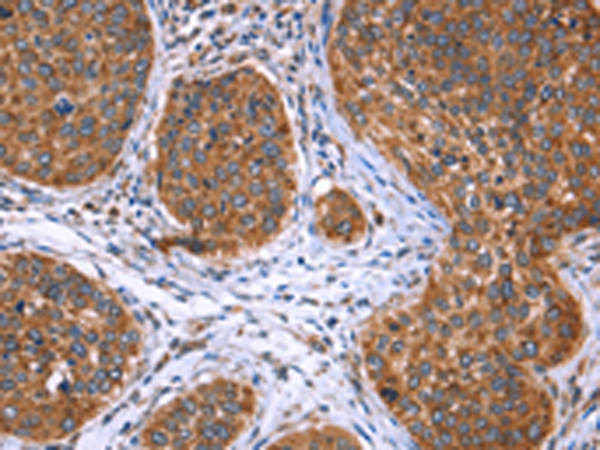

分类: 科研抗体货号: P04874别名: F1AA; F1A-ALPHA; FEM1-beta应用: WB,IHC反应种属: Human, Mouse, Rat